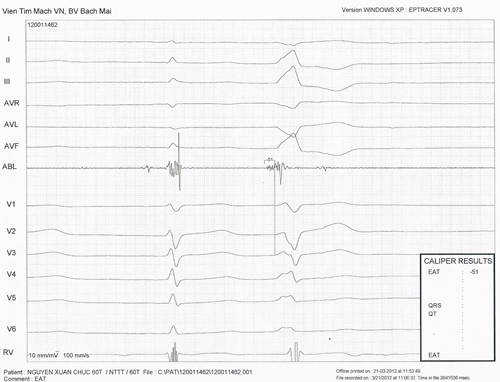

Hình 17: Triệt đốt ngoại tâm thu thất khởi phát từ xoang Valsalva lá vành trái. Xác định vị trí ổ khởi phát bằng phương pháp ghi điện thế sớm nhất. Điện thế thất ghi được ở vị trí đầu điện cực đốt sớm hơn phức bộ QRS trên điện tâm đồ bề mặt 51 ms.